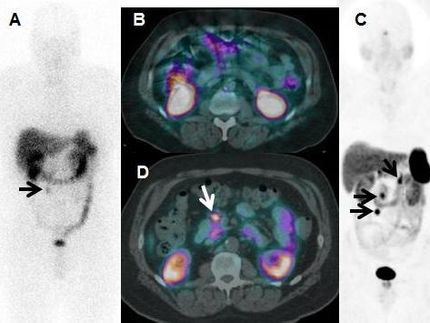

The reconstructed 3D cell tissue is subjected to a PET scan.

The already patented process combines chromatographic principles (separation of substances based on their interactions with a stationary and a mobile phase) with a dynamic 3D cell culture. At the heart of the process is a stationary phase made of biocompatible silk fibroin sponges, which act as an artificial scaffold to immobilize human cells in a three-dimensional structure. A special pump system continuously supplies the cells with nutrients, simulating realistic conditions in human tissue, while the radiopharmaceutical agents are applied and observed in real-time using imaging techniques (µPET/CT, positron emission tomography/computed tomography). This enables a parallel evaluation of radiotracer binding and cellular biochemical processes. First author Verena Pichler from the Department of Pharmaceutical Sciences at the University of Vienna explains: "With our method, we are not only creating an alternative to animal testing, but can also make the development of new radioactive marker substances much more efficient. Our aim is to raise diagnostics and therapy to a new level and improve ethical standards at the same time."